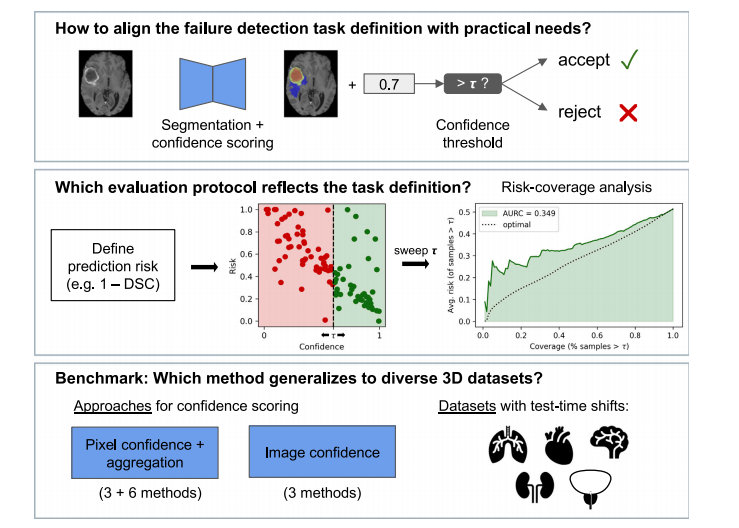

本研究的贡献如下(如图1所示):整合现有评估协议:分析现有方法的不足之处,并提出一个通用且稳健的故障检测评估流程。该流程基于选择性分类(Selective Classification)文献中的风险-覆盖分析(Risk-Coverage Analysis),以减轻已识别的评估问题。引入一个基准测试框架:该框架包含多个公开可用的三维放射学数据集,以评估故障检测方法在单一数据集之外的泛化能力。我们的测试数据集涵盖了现实世界中的分布变化,以模拟可能导致分割失败的因素,从而进行更全面的评估。比较不同类别的故障检测方法:在该基准测试框架下,我们比较了多种故障检测方法,包括图像级方法和像素级方法(后续通过聚合转换为图像级)。结果表明,基于预测集成(ensemble predictions)之间的配对Dice系数(Roy et al., 2019)在所有比较方法中表现最佳,因此我们推荐该方法作为未来研究的强基线。

Fig. 1. Overview of the research questions and contributions of this paper. Based on a formal definition of the image-level failure detection task, we formulate requirements for theevaluation protocol. Existing failure detection metrics are compared and the risk-coverage analysis is identified as a suitable evaluation protocol. We then propose a benchmarkingframework for failure detection in medical image segmentation, which includes a diverse pool of 3D medical image datasets. A wide range of relevant methods are compared,including lines of research for image-level confidence and aggregated pixel confidence, which have been mostly studied in separation so far.

图1. 本文的研究问题和贡献概述。基于图像级故障检测任务的正式定义,我们制定了评估协议的要求。对现有的故障检测度量进行比较,并确定风险覆盖分析作为合适的评估协议。接着,我们提出了一个医学图像分割中故障检测的基准测试框架,其中包括多样化的3D医学图像数据集。比较了广泛相关的方法,包括图像级置信度和聚合像素置信度的研究方向,而这两者迄今为止大多是分开研究的。